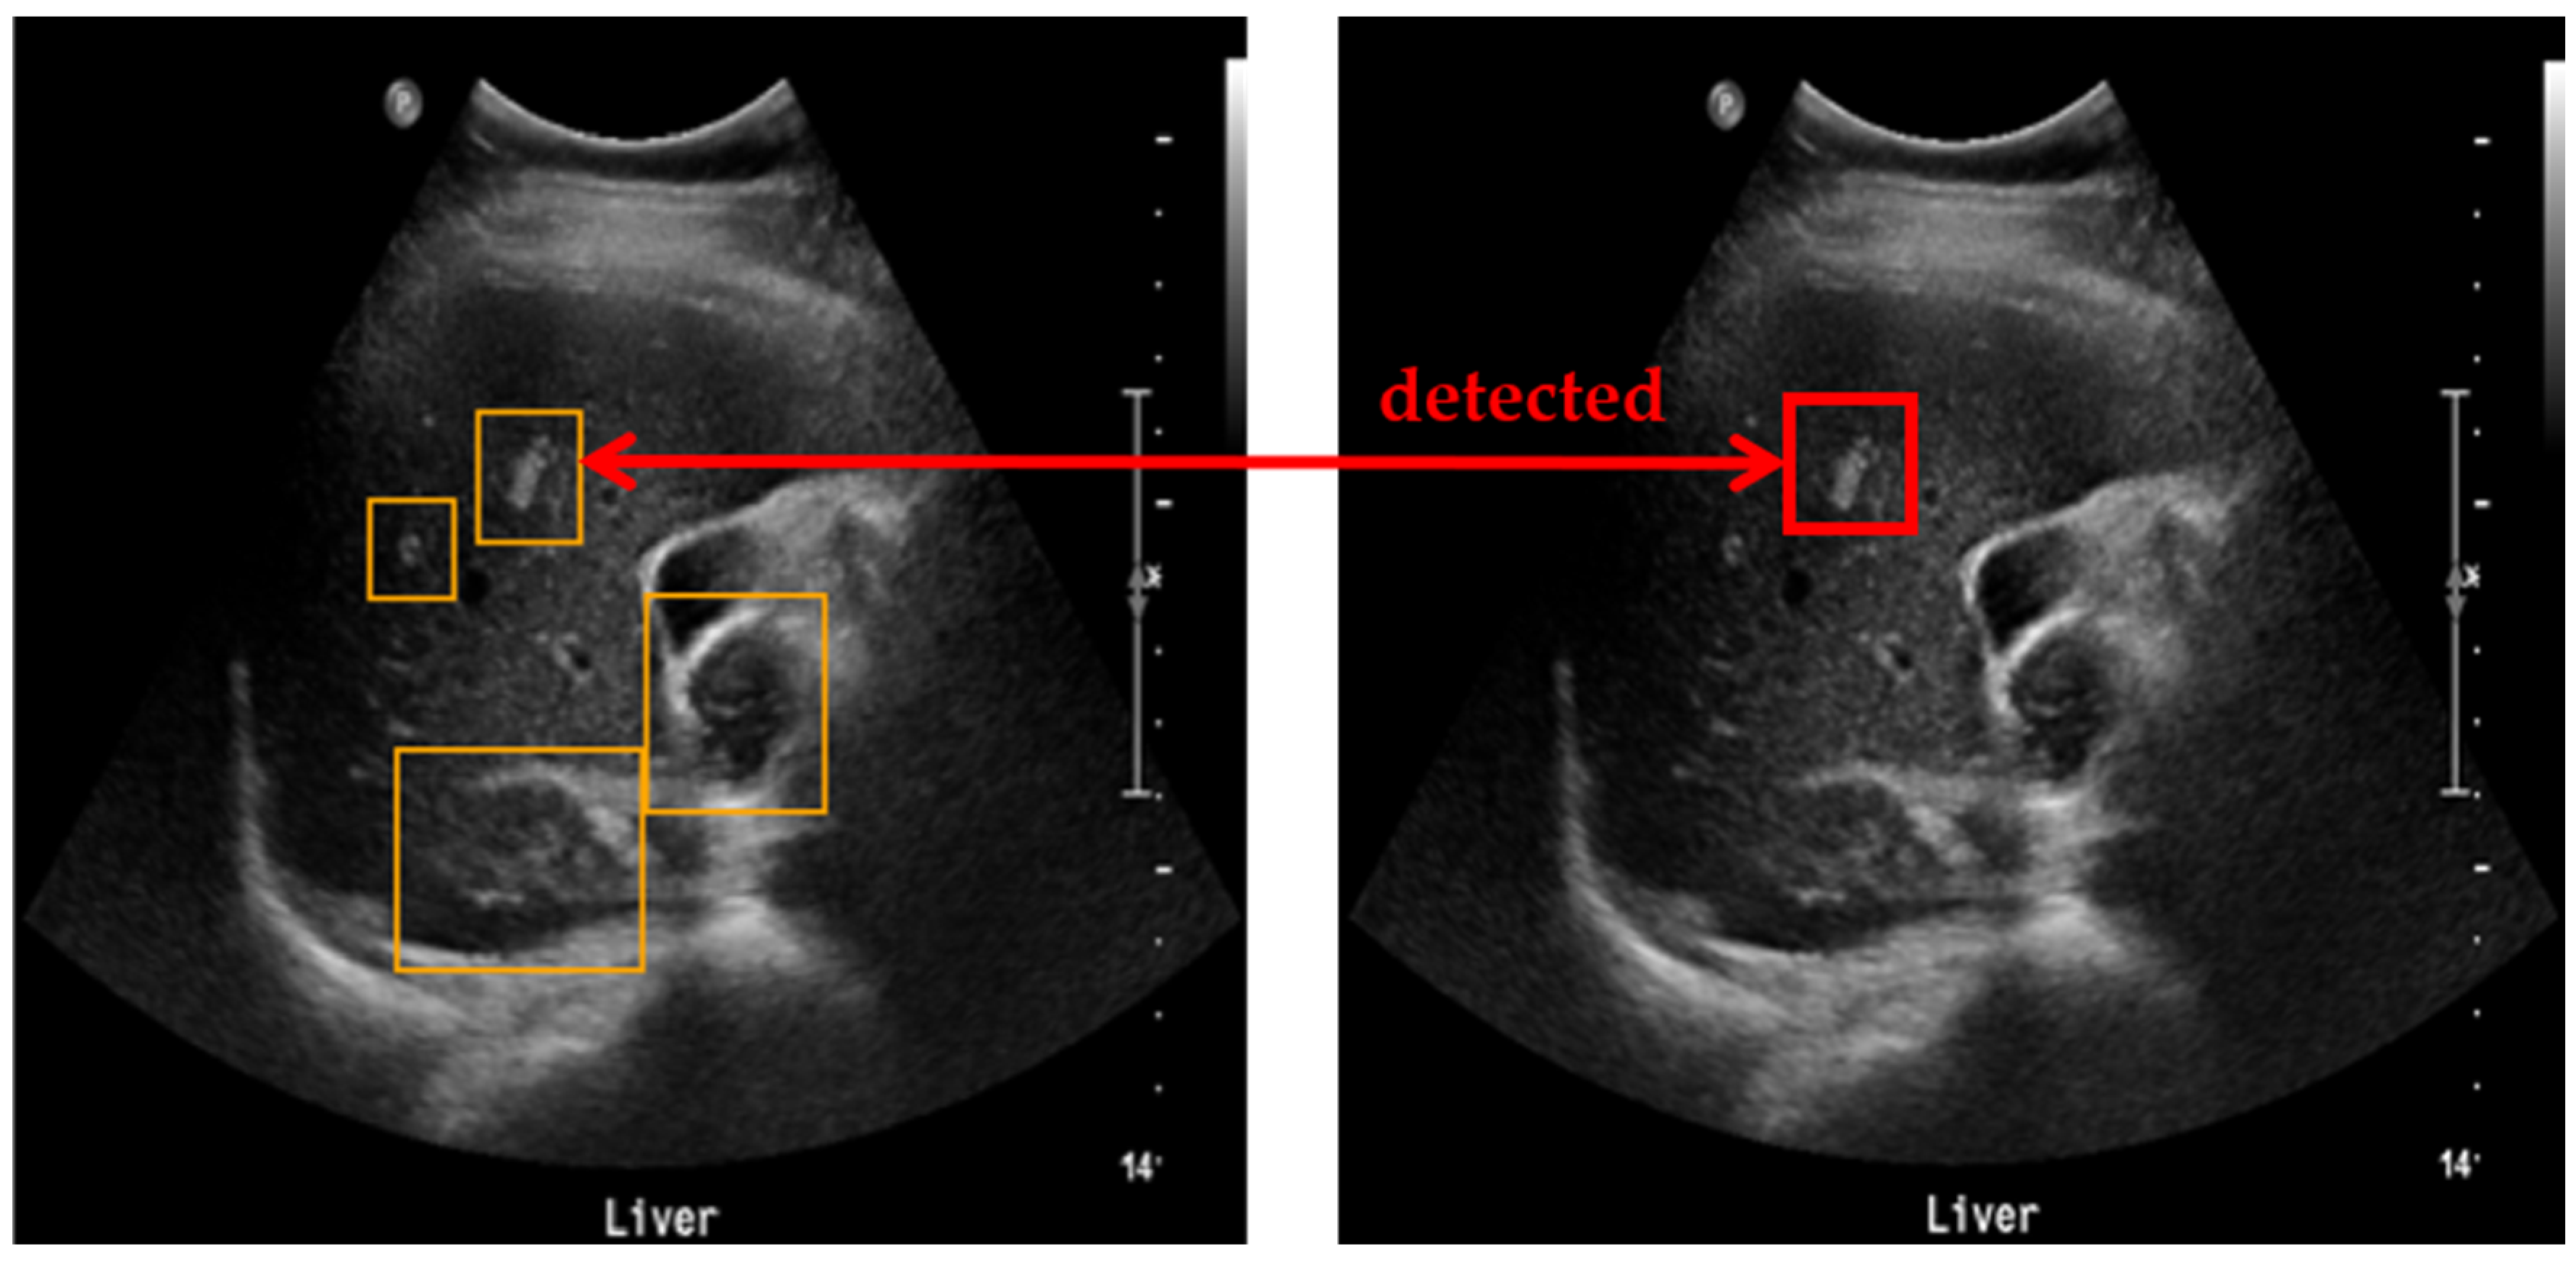

To evaluate the accuracy of lesion detection after applying clustering, SM-WBF, and padding, a novel measurement method was introduced. The primary goal was to ensure that all regions suspected of being lesions were identified, minimizing the chances of missing any lesions. As illustrated in Figure 5, all detected lesion-suspected regions were compared with the ground truth, and if at least one box matched, the detection was considered successful. A match was determined by comparing the IoU between the detected box and the ground truth box including padding. An IoU of 0.9 or higher was used as the threshold for a match, ensuring high precision in detection evaluation (Figure 6).

Figure 6.

Method for measuring lesion detection accuracy. Among the four detected bounding boxes, at least one box has an IoU of 0.9 or higher with the ground truth, and, therefore, the detection is considered successful.